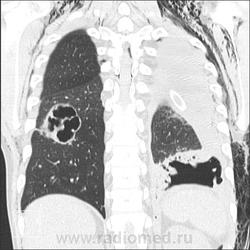

Мужчина, 31 год. ВИЧ+, на учёте 1,5 года, прекратил употреблять наркотические средства около года назад, получает специфическое противовирусное лечение. Носитель гепатита С (обострение в марте, хотели после лечения выписать, но вдруг затемпературил). Динамика с 23 марта по 18 апреля. Состояние с 8 апреля оценивается как тяжелое, боковые снимки с динамической нерезкостью.

КТ от 18.04:

Норма в марте (с усилением рисунка в базальных отделах справа без предыдущих снимков можно поспорить). Затем абсцедирующая пневмония в S6 справа и S8-9-10 слева. Затем напряженный пневмоторакс слева с малым|средним гидротораксом. На контроле левое легкое частично расправлено, уровень жидкости до 6 ребра по задней подмышечной линии. Последний - больших размеров пневмоторакс слева, выраженная эмфизема мягких тканей и пневмомедиастинум.

После контроля 18 апреля взяла на КТ. Изображения в начале темы. Есть вопрос: подскажите, пожалуйста, каким анатомическим путём воздух попал в эпидуральное пространство?